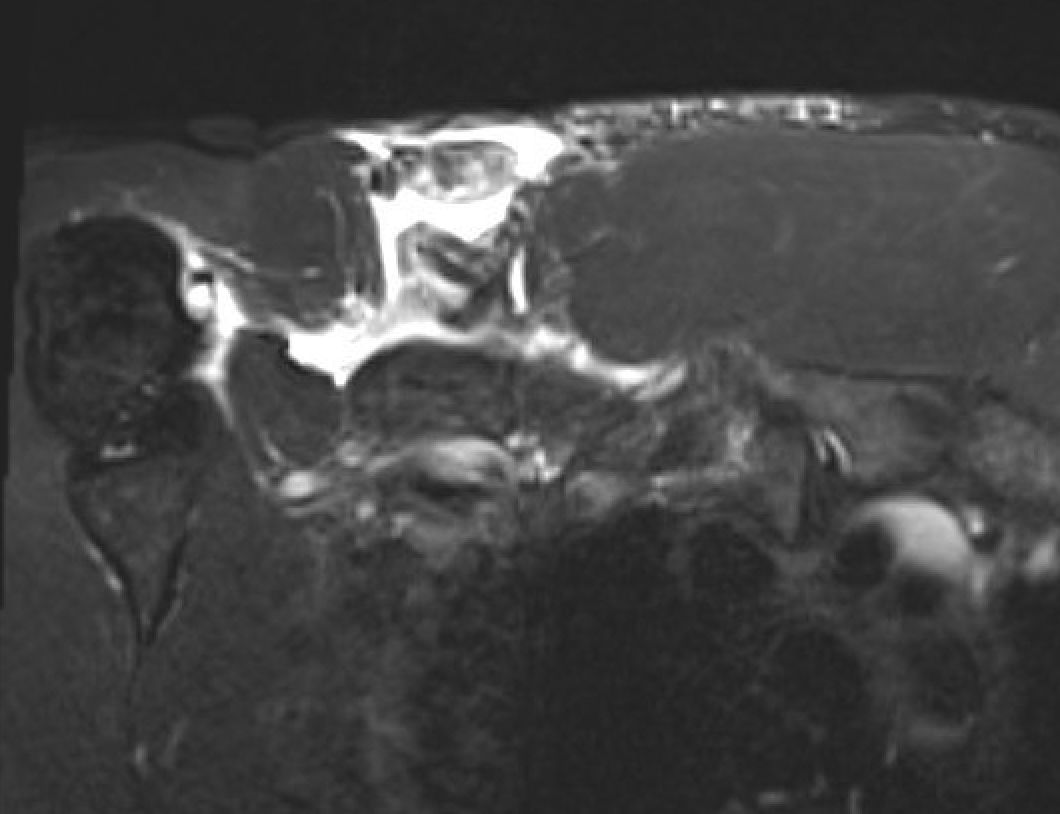

MRI

Coronal T2 Right shoulder demonstrating tendon avulsion of both sternal and clavicular heads

Axial T2 Right shoulder demonstrating tendon avulsion of both sternal and clavicular heads

Coronal T2 MRI Right shoulder demonstrating musculotendinous avulsion